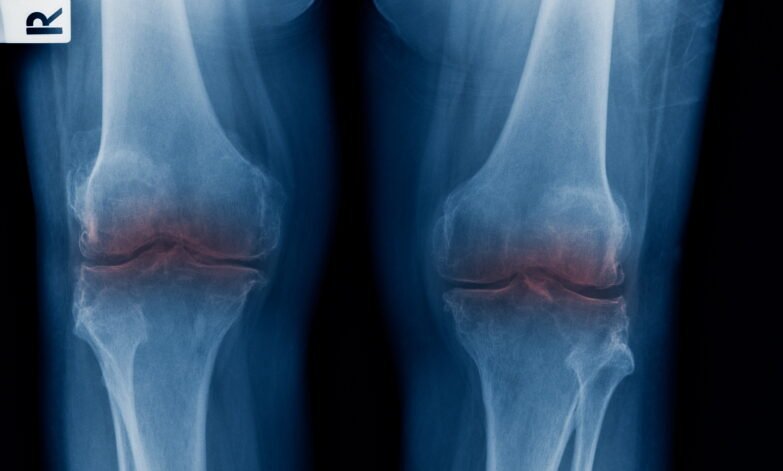

Knee Arthritis